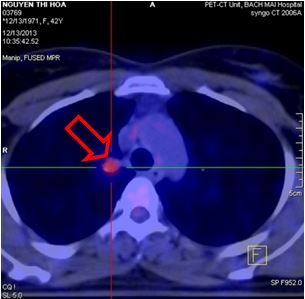

1. Chụp cắt lớp vi tính lồng ngực: Hình ảnh tràn dịch màng phổi phải, hạch trung thất (hình 1a)

Hình 1a: Hình ảnh chụp cắt lớp vi tính lồng ngực thấy tràn dịch khoang màng phổi phải (đầu mũi tên đỏ), khó đánh giá hạch trung thất (trong vòng tròn đỏ).

Hình 1b: Trên hình ảnh PET/CT sau 1 tháng điều trị thấy hạch trung thất kích thước 0,9 cm, max SUV=2,8 (đầu mũi tên đỏ), do bệnh nhân không chụp PET/CT trước điều trị nên khó đánh giá hạch trung thất mới xuất hiện sau điều trị hay hạch nhỏ đi sau điều trị, giả thiết hạch nhỏ đi sau điều trị phù hợp hơn do trên phim chụp CT ngực 64 dãy sau 5 tháng điều trị (xem hình số 10) không còn thấy hạch trung thất.

1. Chụp PET/CT sau điều trị 1 tháng:

Nhu mô hai phổi không thấy tổ chức hấp thu F-18 FDG bất thường, không thấy tràn dịch màng phổi.

- Hạch rốn phổi phải đường kính 0,9cm, tăng hấp thu F-18 FDG, max SUV=2,8.

- Xương chậu phải tăng hấp thu F-18 FDG, max SUV=6,17

Hình khuyết xương thân D10 không tăng hấp thu F-18 FDG

Hình 9: Hình ảnh PET/CT sau điều trị 1 tháng cho thấy hạch trung thất kích thước 0,9 cm tăng hấp thu F18-FDG với max SUV=2,8 (đầu mũi tên vàng), xương chậu phải tăng hấp thu F18-FDG với max SUV=6,17 (đầu mũi tên đỏ)